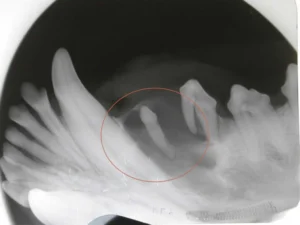

Possible causes for a missing tooth include congenital absence (never formed), non-eruption (present below the gum line but didn’t come in), or tooth defects/malformation. Anytime a missing tooth is discovered, an intra-oral radiograph (x-ray) is indicated. Because anesthesia is needed to obtain good dental x-rays, the spay/neuter surgery around 6 months of age is an ideal time for performing x-rays.

If unerupted teeth are discovered at an early age (ideally before one year of age) when eruptive potential is still present , surgery of the gum can be performed to help encourage tooth eruption. For unerupted teeth in animals beyond a year of age, surgical exploration and extraction are recommended because the tooth will not erupt. Impacted teeth that are not removed can contribute to dentigerous cyst formation. These cysts can grow very large and cause damage to other teeth and surrounding bone. If a cyst forms, treatment involves surgical removal of the impacted tooth and cystic lining.

An area with an apparently missing tooth (circled above) began to show swelling. An x-ray of the area demonstrated a tooth that never erupted with an associated cyst. Because cysts may expand and cause damage to surrounding structures, oral surgery was performed to remove the entire cyst and unerupted tooth.